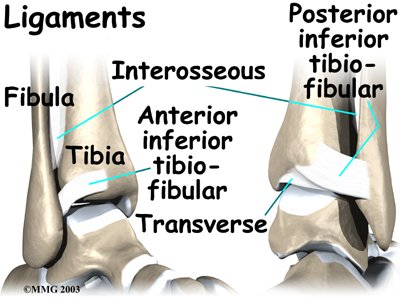

The ankle syndesmosis is supported and held together by three main ligaments. The ligament crossing just above the front of the ankle and connecting the tibia to the fibula is called the anterior inferior tibiofibular ligament (AITFL). The posterior fibular ligaments attach across the back of the tibia and fibula. These ligaments include the posterior inferior tibiofibular ligament (PITFL) and the transverse ligament.

The ankle syndesmosis is supported and held together by three main ligaments. The ligament crossing just above the front of the ankle and connecting the tibia to the fibula is called the anterior inferior tibiofibular ligament (AITFL). The posterior fibular ligaments attach across the back of the tibia and fibula. These ligaments include the posterior inferior tibiofibular ligament (PITFL) and the transverse ligament.

The interosseous ligament lies between the tibia and fibula. (Interosseous means between bones.) The interosseus ligament is a long sheet of connective tissue that connects the entire length of the tibia and fibula, from the knee to the ankle.

The syndesmosis ligaments hold the bottom ends of the tibia and fibula in place. This arrangement forms the upper surface of the ankle joint. The ankle joint is a hinge joint. The hinge is formed where the tibia and fibula sit above the talus bone. This connection is called a mortise and tenon, a stable connection that woodworkers and craftsmen routinely use to create strong and stable constructions.